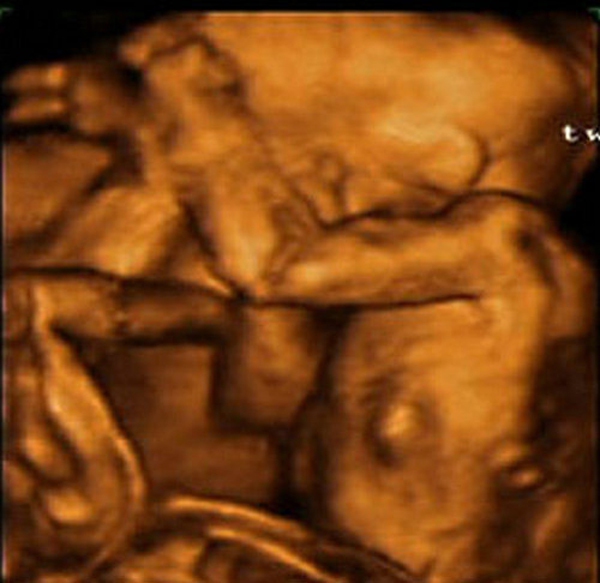

Đến ảnh chụp 4D sống động

Những hình ảnh siêu âm bốn chiều cho thấy các em bé đang nằm ngủ rất ngoan trong bụng mẹ